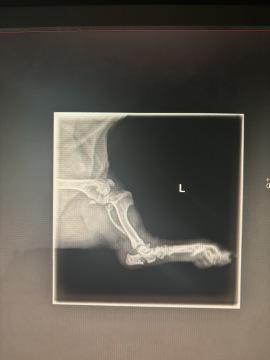

Po nehodě jsme s ní okamžitě jeli k veterináři, který udělal základní vyšetření a rentgen. Na základě toho se zjistilo se, že její zranění jsou bohužel hodně vážná, a ještě tu noc jsme ji

odvezli na specializovanou kliniku v Hradci Králové. Zde ji stabilizovali a vyloučili život ohrožující poranění.

Potvrdili těžkou zlomeninu kloubní kosti u paty, nalomenou pánev a zlomenou nožičku.

Veterináři nám nabídli dvě možnosti: buď artrodézu (trvalé znehybnění kloubu), která by omezila její pohyblivost, nebo osteosyntézu (operační léčbu zlomenin pomocí kovových implantátů). Jelikož CT vyšetření ukázalo, že kloub je možné opravit, rozhodli jsme se dát Dorotce šanci na plnohodnotný život.